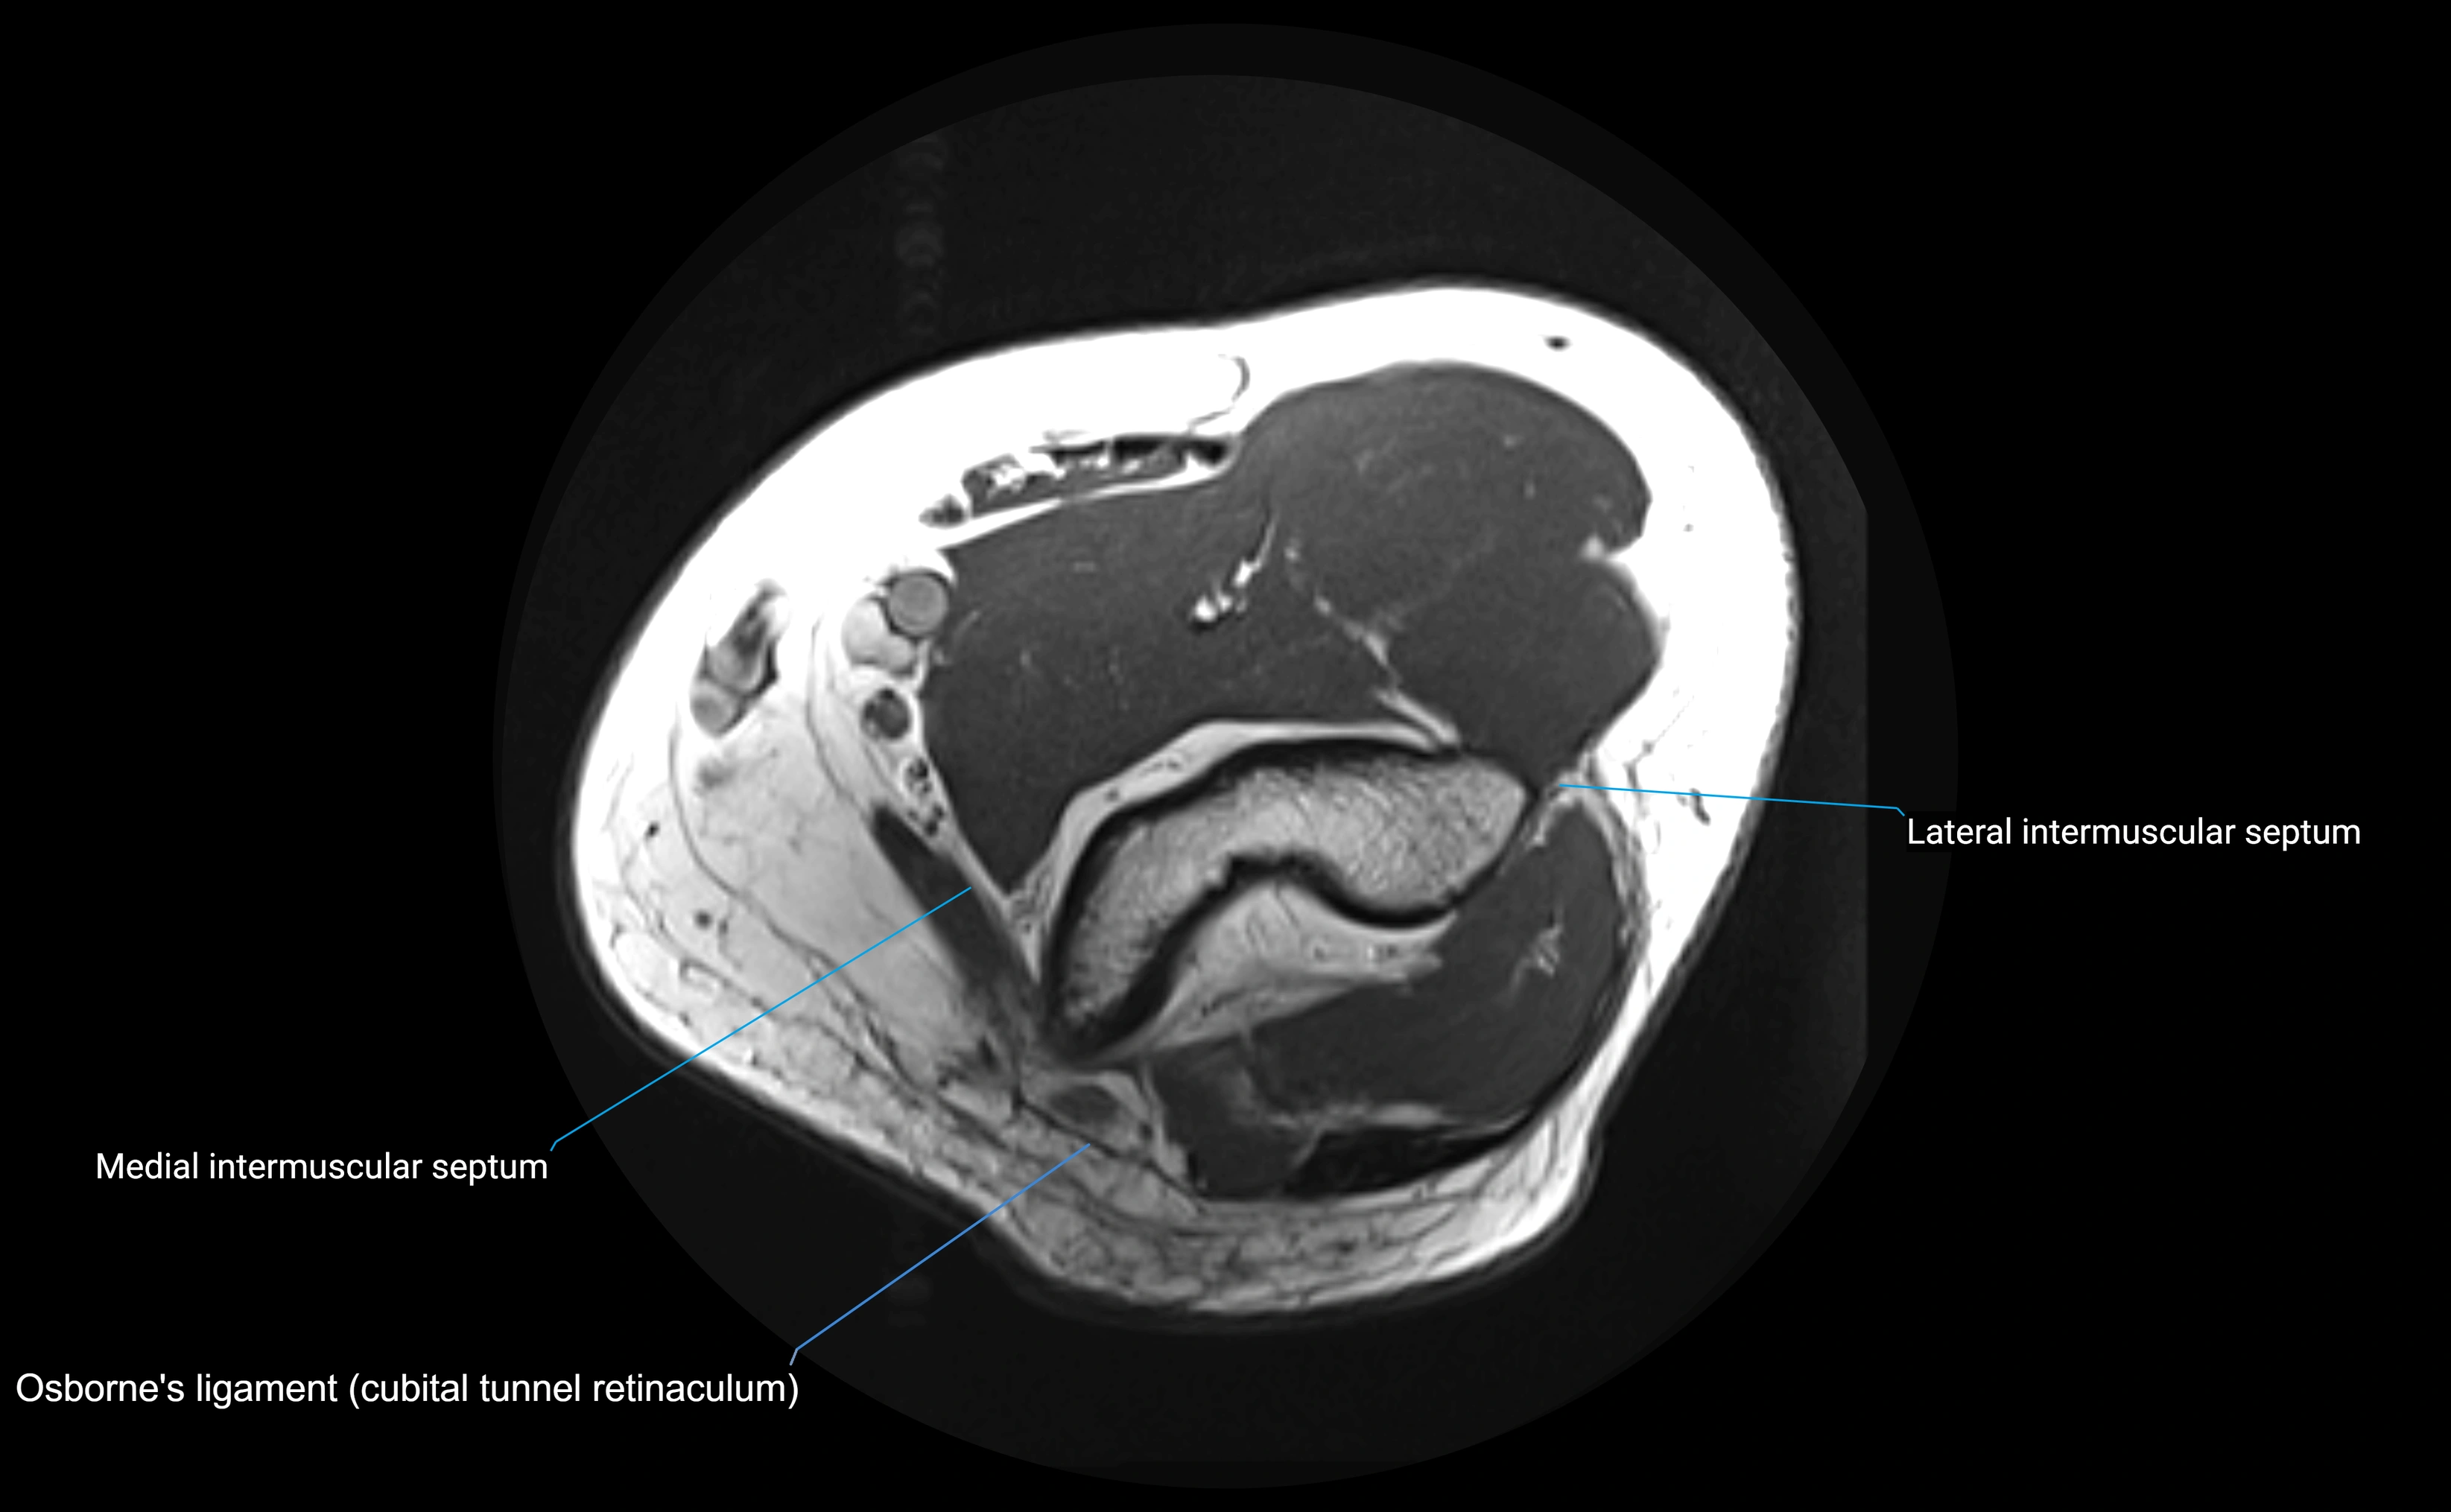

MRI Appearance

T1-weighted images:

• Ligament: low signal intensity (dark), appearing as a continuous band around the radial head.

• Adjacent fat and marrow: bright, creating contrast with the ligament.

• Thickening or disruption indicates injury or fibrosis.

• Joint capsule and synovium seen as thin low-signal lines contiguous with ligament margins.

T2-weighted images:

• Ligament: low signal (dark) with clear delineation from joint fluid.

• Fluid or edema: bright hyperintense, separating or surrounding the ligament in partial tears.

• Complete tear: discontinuity or non-visualization of ligament fibers, often with joint effusion.

STIR:

• Normal ligament: dark band encircling radial head.

• Pathology: bright hyperintense periligamentous signal suggesting edema, sprain, or partial tear.

Proton Density Fat-Saturated (PD FS):

• Normal: dark, well-defined band outlining the radial head.

• Partial tear: irregular or bright hyperintense signal within or adjacent to ligament fibers.

• Joint effusion and reactive synovitis appear bright and are well visualized.

MRI images

image